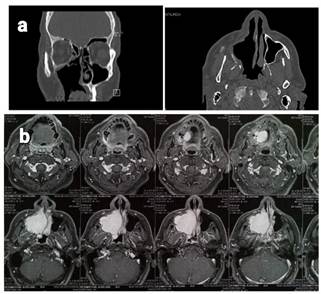

Computed

tomography (CT) scan showed a right maxillary sinus soft-tissue density mass

which was destructive in nature with maximal length of about seven centimeters

occupying the whole right maxillary sinus and ipsilateral nasal cavity

extending to oral cavity with bony destruction of medial maxillary sinus wall,

right nasal turbinates, nasal septum and right hard palate but sparing orbital

floor.

Magnetic

resonance imaging (MRI) with and without gadolinium demonstrated a T1

hypointensity and T2 hyperintensity with a bright mass on T1

with contrast within right maxillary sinus and nasal cavity extending to

ethmoid cells superiorly and oral cavity inferiorly (Figure 4b).

by regular visits and CT scans (Figure 4a).

Figure

4. Coronal and

axial view of paranasal sinuses CT scan one year post operation, No evidence of

recurrence is seen (a). Axial T1 with gadolinium injection

before surgery demonstrates a bright mass (b).